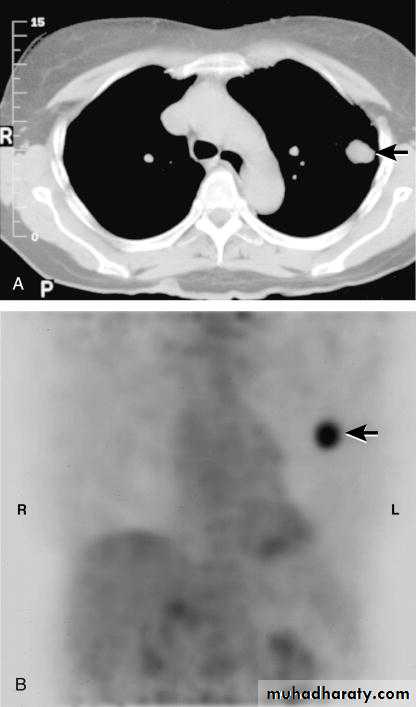

Radiology..Computerized Tomography CT- chest

Add more detailed anatomical information and detect pulmonary lymph node enlargement more clearly.

Positron Emition tomography (PET)

May shows markedly increased activity at the same area, indicative of very high metabolic activity and a high probability of malignancy.2013